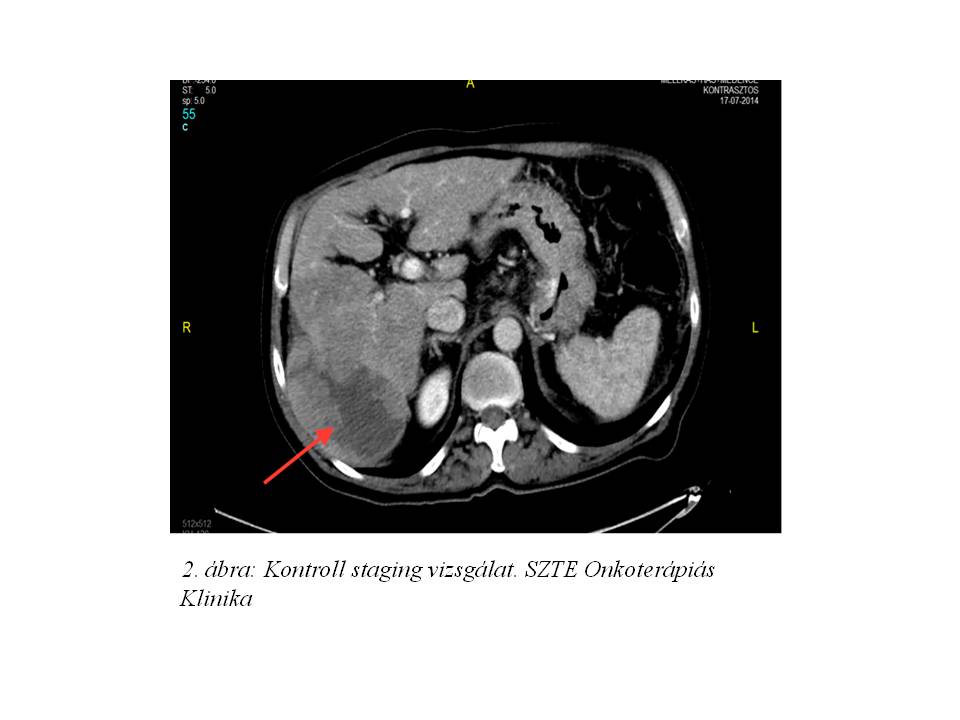

A sigma tumor rutin követése kapcsán 2014 márciusában készült hasi és kismedencei CT vizsgálat, mely a máj VII. szegmentumában egy 80 mm-es, a VI. szegmentumban pedig egy 35 mm-es laesiot igazolt, melyek metastasisok gyanúját vetették fel. A colorectalis tumorra specifikus markerek azonban nem emelkedtek. A beteg referálásra került az egyetem gasztrointesztinális onkoteamjében, ahol a CT felvételek ismételt áttekintése során felvetődött a primer hepatocellularis carcinoma lehetősége. Ezt követően a nagyobb lézióból UH vezérelt biopszia történt, mely primer hepatocelluláris carcinoma jelenlétét igazolta. Ezt az emelkedett szérum AFP szint is megerősítette (2014.04.04: 1053 µg/L) (1. ábra).

A multidiszciplináris onkoteam döntése alapján sebészi eltávolítás, illetve a jobb vena hepatica érintettsége miatt TACE (transarterialis chemoembolisatio) kezelés nem jött szóba. A vizsgálatok szerint a beteg hepatocelluláris karcinómája BCLC “C” (The Barcelona Clinic Liver Cancer staging) stádiumú volt, a hepatikus funkciók szempontjából pedig a Child-Pugh pontrendszer besorolása szerint az “A” osztályba tartozott, így sorafenib (Nexavar) monoterápiája indult 2014 áprilisában. A beteg 3 ciklust kapott meg. Azt ezt követően készült kontroll staging vizsgálatok azonban a betegség RECIST 1.1 szerinti 36%-os progresszióját igazolták. Az AFP szint 1388 µg/L-re emelkedett. A kezelt HCC nagyobbik góca a progresszió során áttörte a máj dorsolaterális tokját, mely a megfelelő régióban tapintható terimét hozott létre (2. ábra). A progresszió miatt a beteg sorafenib kezelése 2014 júliusában felfüggesztésre került.